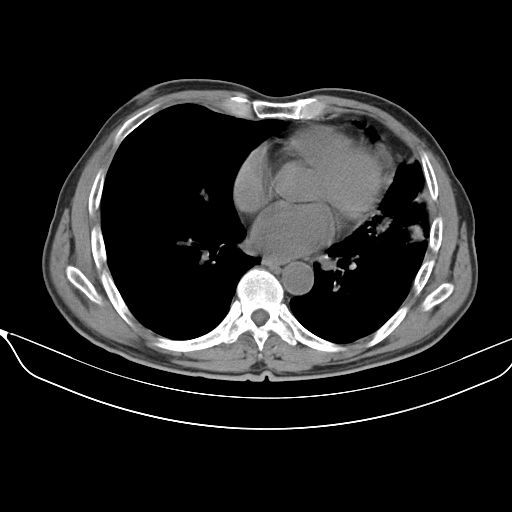

以下是引用心路寻觅在2010-3-1 10:23:00的发言:[br]1、考虑左肺上叶周围型肺癌[br]2、右上肺陈旧性病灶。[br][br][本贴已被 心路寻觅 于 2010-3-1 10:40:18 修改过]

以下是引用shuiyuan在2010-3-1 10:45:00的发言:[br]考虑左肺上叶中心型肺癌伴阻塞型炎症,邻近胸膜受侵。